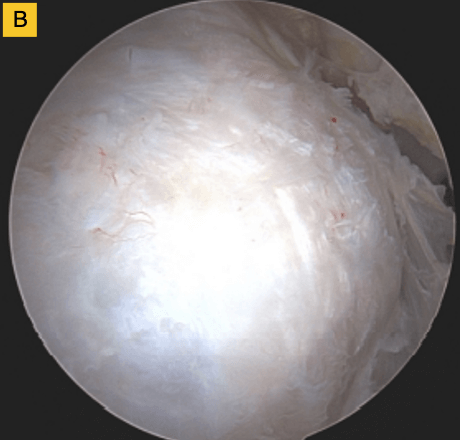

Down the road, this patient was having some bicipital pain, so we took the opportunity to look at the repair visually and performed a biceps tenodesis. You can see in this image, there's cabling of the fibers coming down onto the footprint and you can no longer see the scaffold… it’s been completely incorporated into the repair. For this patient, that was a pretty remarkable event.

(A) Tendon fibers can be seen inserting on to footprint in an organized fashion. Visible, prominent suture easily removed.

(B) BioBrace® well-synovialized and completely incorporated into the rotator cuff with new native tissue in and around the implant.